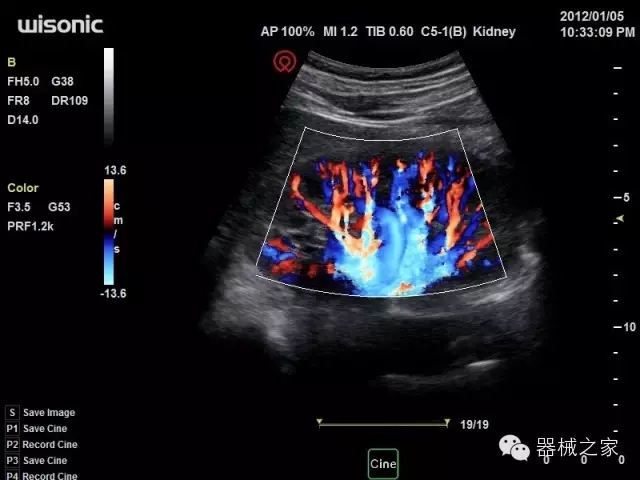

臨床圖片賞析

產(chǎn)品特點(diǎn)

·全球目前唯一一款配備主機(jī)雙探頭接口,整機(jī)重量(含電池)在5公斤以內(nèi)的便攜式彩超;

·一款互聯(lián)網(wǎng)彩超,只要有手機(jī)信號(hào)的地方就可以非常方便地實(shí)現(xiàn)遠(yuǎn)程會(huì)診和病案調(diào)取;

·鎂鋁合金外殼,堅(jiān)固可靠耐用;

·獨(dú)有的HoloTM PW 實(shí)時(shí)3取樣門(mén)PW成像技術(shù),精確進(jìn)行血管診斷;

·一鍵優(yōu)化B、Color、PW,Auto Doppler自動(dòng)識(shí)別血管位置、偏轉(zhuǎn)角度等,提高工作效率;

·30°超廣角精細(xì)偏轉(zhuǎn)成像技術(shù),更優(yōu)異的頻譜圖像;

·W+智能搜索引擎,快速尋找圖像;

·SSD、USB3.0保障開(kāi)機(jī)快,導(dǎo)出圖像更快,減少等待時(shí)間;

·WIFI、網(wǎng)口、3G,多重聯(lián)網(wǎng)方式,全天候保障云端備份,不再擔(dān)心圖像丟失;